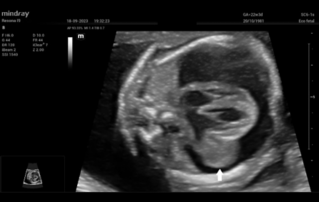

Female pelvic floor anatomy, which developed since the early 20th century, has had a variety of theories, including integral theory, three levels of vaginal support theory, "hammock hypothesis", and three-chamber system. Supporting structures such as pelvic floor muscles, fascia and ligament play an important role in maintaining the normal function of pelvic floor, among which levator ani muscle group is one of the most important supporting structures.